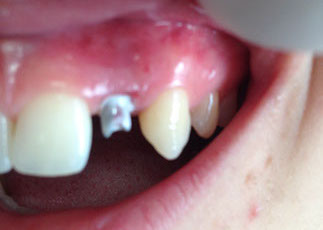

agenesia di un incisivo laterale